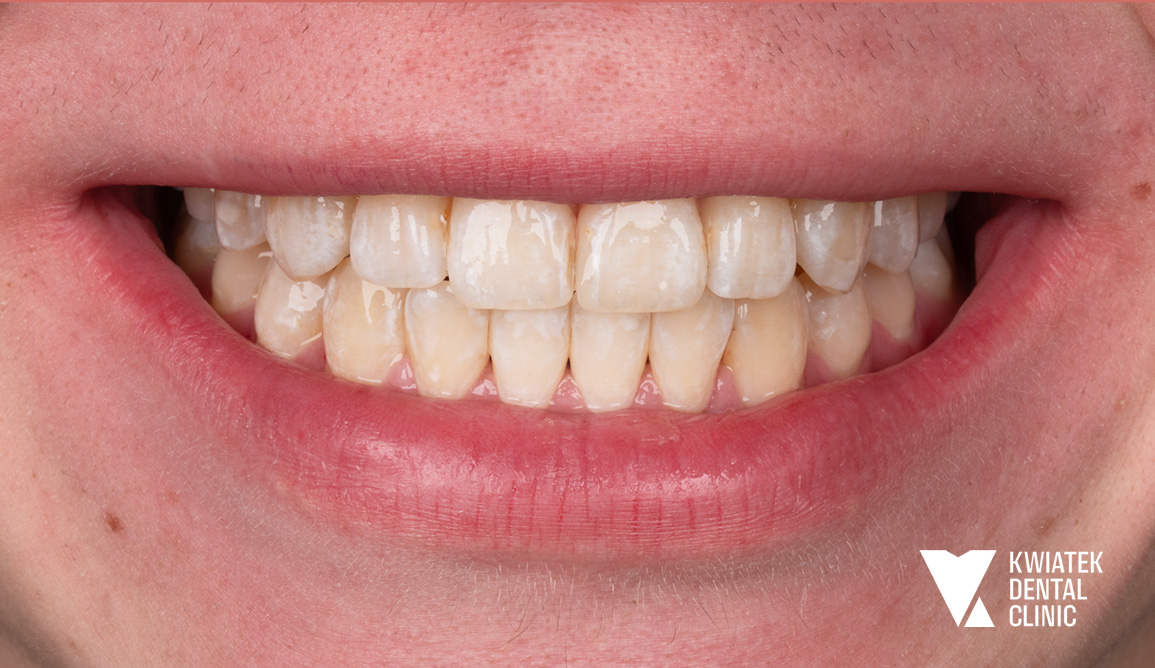

Kobieca harmonia - naturalna metamorfoza pełna światła i finezji

Pani Hanna zgłosiła się z uśmiechem naznaczonym wieloletnimi wypełnieniami, przebytym leczeniem ortodontycznym oraz zaburzoną funkcją zgryzu. Po kompleksowej diagnostyce, starannym przygotowaniu tkanek i profesjonalnym wybielaniu wykonano precyzyjny remodeling zębów metodą flow injection, który przywrócił naturalne proporcje, świetlistość i harmonię łuków zębowych. Rezultatem jest metamorfoza subtelna, a zarazem wyraźnie odmieniająca wyraz twarzy, uśmiech jasny, elegancki i w pełni naturalny, podkreślający kobiecą delikatność oraz ponadczasową estetykę.